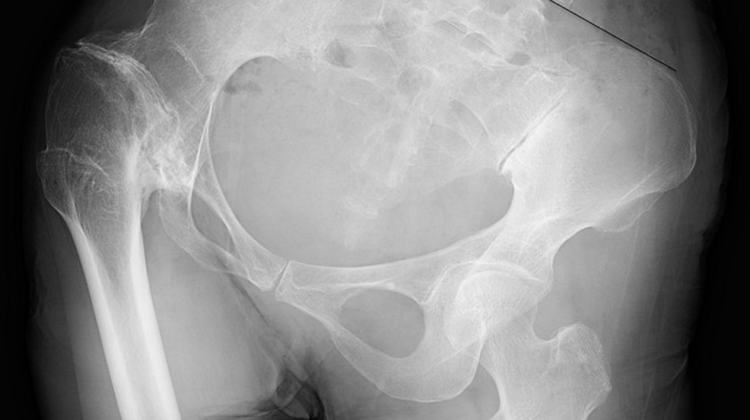

تصوير بالأشعة السينية لتحديد زاوية كوب (Cobb Angle) ودرجة دوران الحوض.